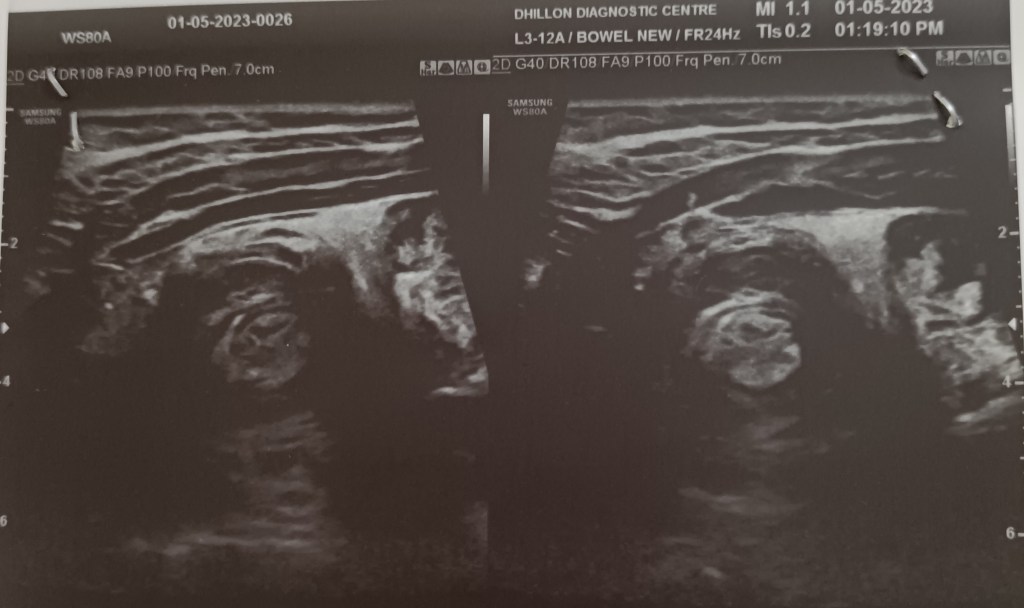

A 7 years old male child admitted with acute abdominal pain showed classic signs of target sign/doughnut sign/pseudo-kidney signs on ultrasound and a mass effect in right iliac fossa on CT. However, the child’s condition improved rapidly and in a few hours he became clinically better and pain free, suggesting spontaneous reduction of the intussusception. Recovered completely on conservative treatment and was not operated.